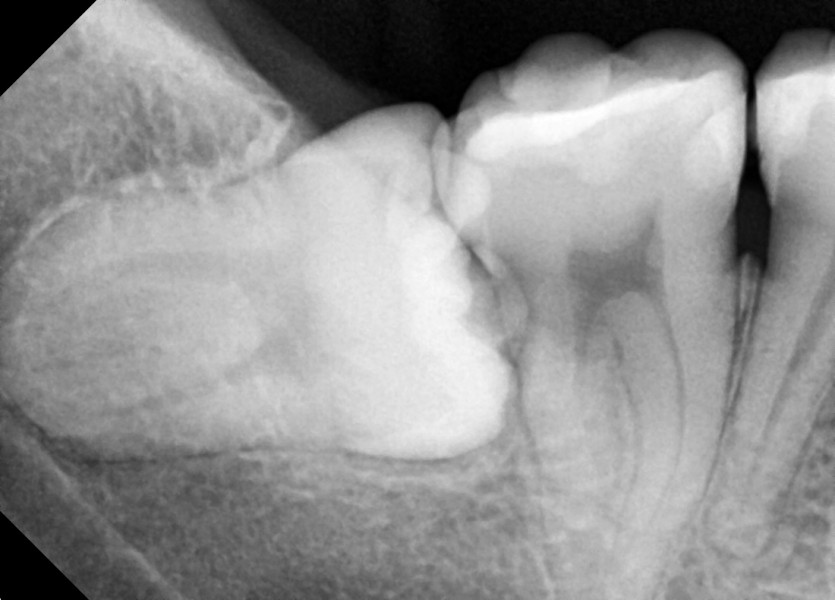

#48 사랑니 발치

구강 외과 전문의가 당일 발치했습니다.